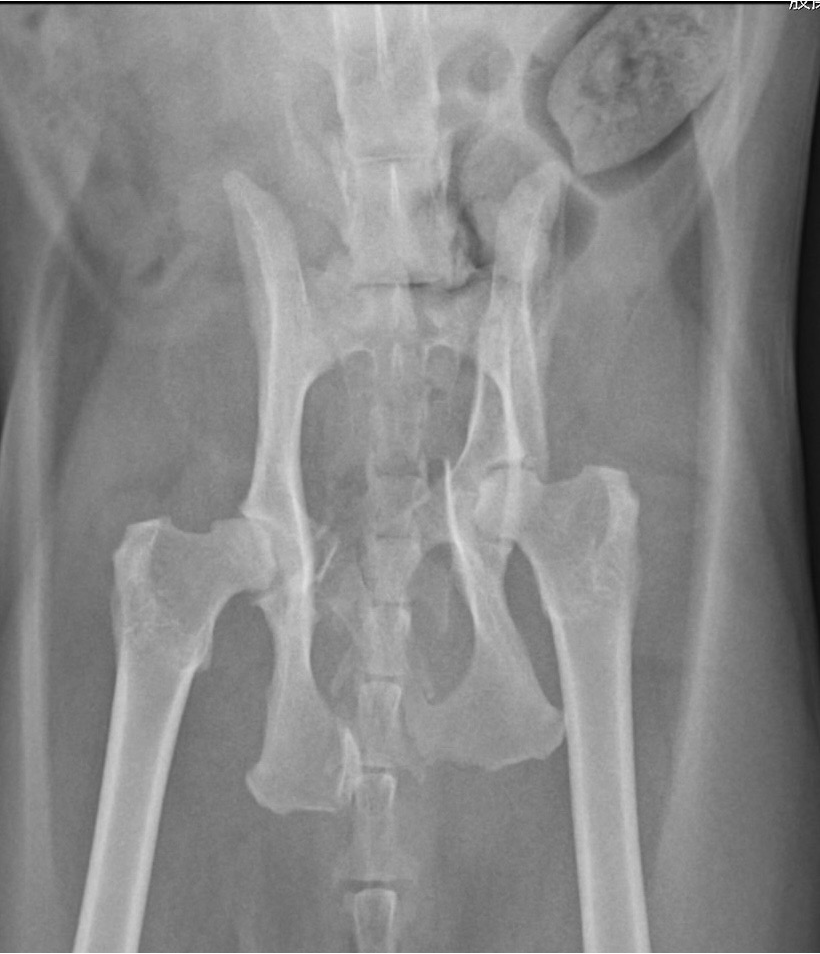

この症例は車で下半身を轢かれてしまい「左の腸骨、恥骨、坐骨の骨折」と診断しました また尿路の損傷を検査するために尿路造影検査も行っています。

整復前の骨盤骨折のレントゲン